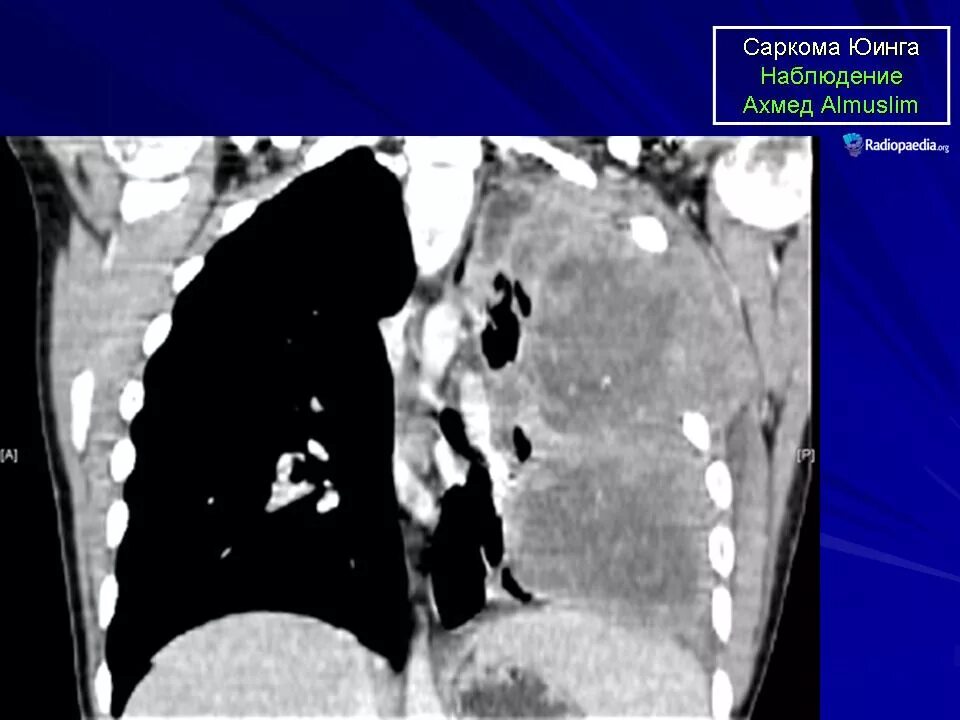

Метастазы плевры